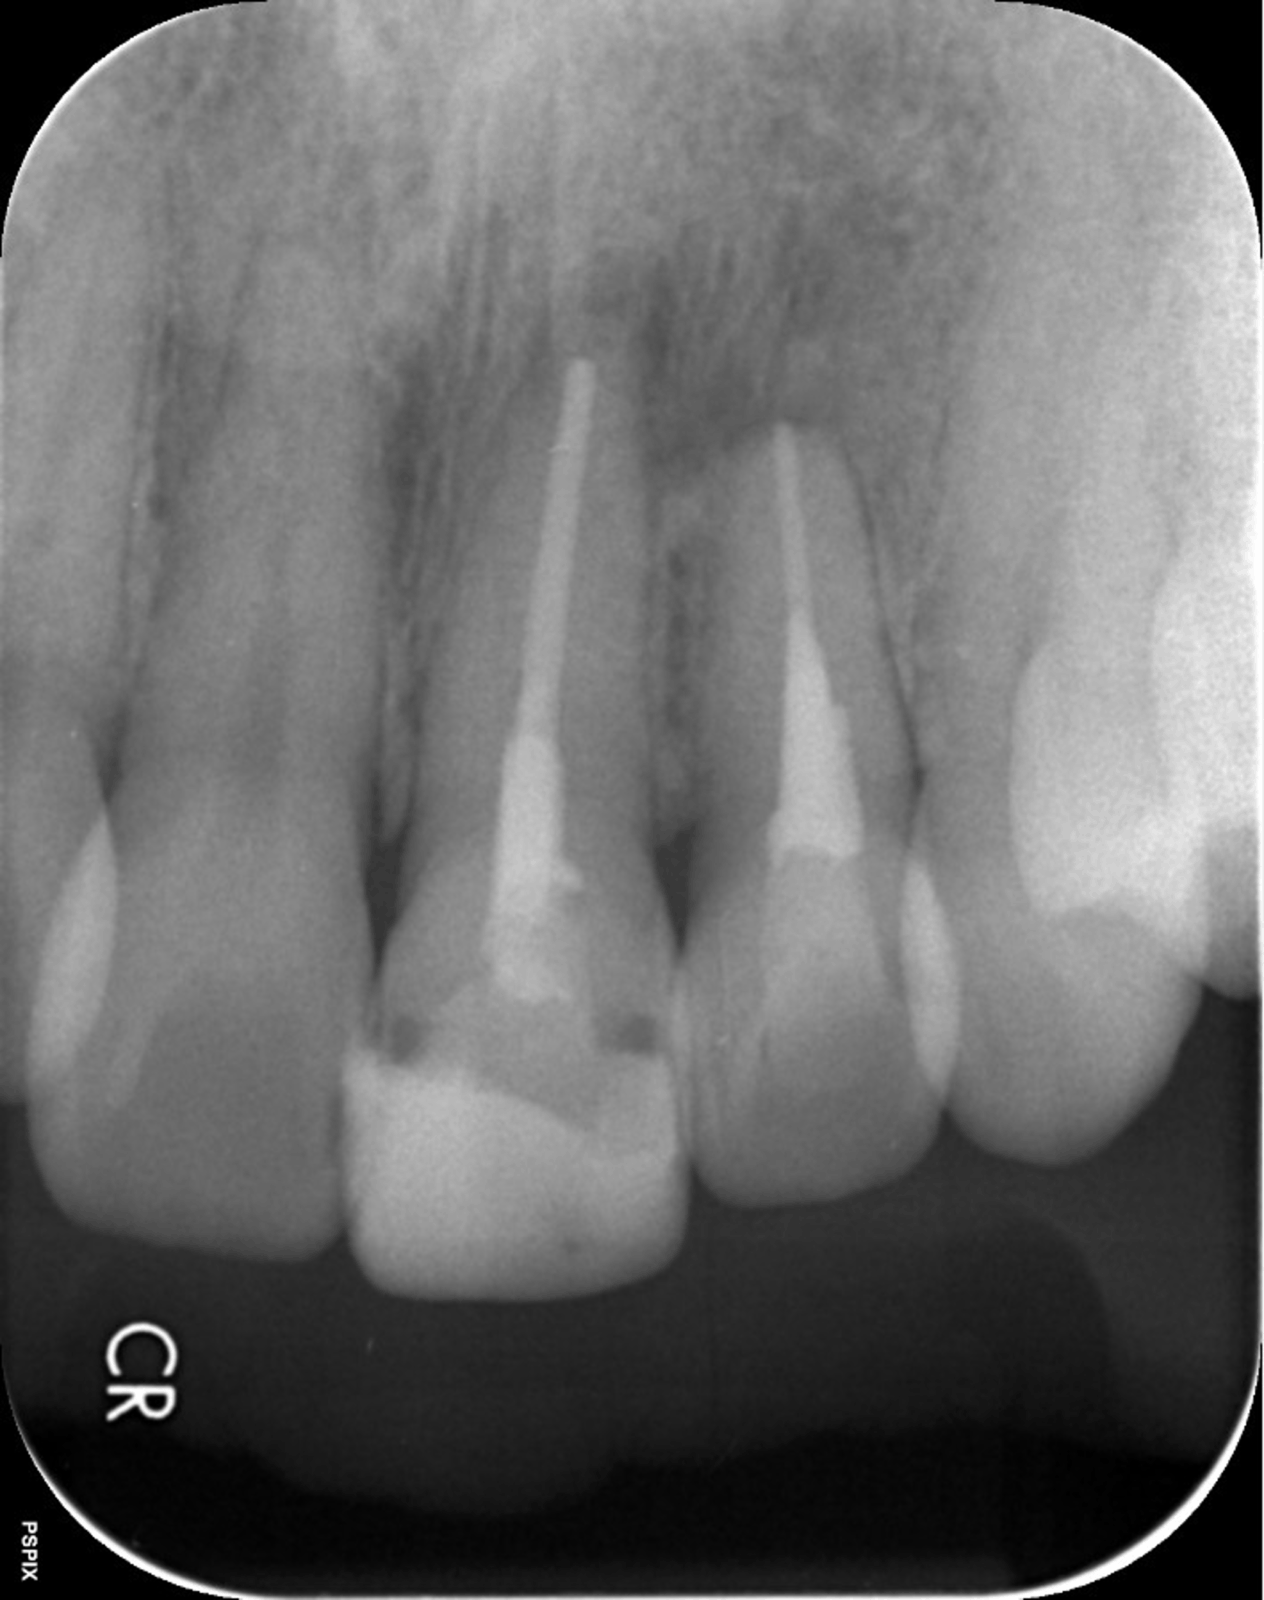

根の先端の炎症を治療する「歯根端切除術」

根の先端に膿が溜まる状況を「根尖病巣」と言います。この状態になると多くが「抜歯宣告」されます。しかし「歯根端切除術」という術式で、抜歯をせずに治療できる場合があります。

歯根端切除術では、歯茎の外側を外科的に切り開き、歯の根の先端ごと膿の袋を取り除きます。取り除いた後の空洞は血液で満たされ、時間の経過と共に再生した骨で埋められます。

• 治療前

• 治療後